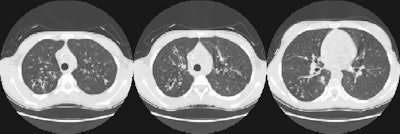

The high resolution CT images also demonstrate the characteristic findings of cystic fibrosis with bronchiectasis and branching peripheral densities indicative of dilated, debris/mucous filled bronchi.